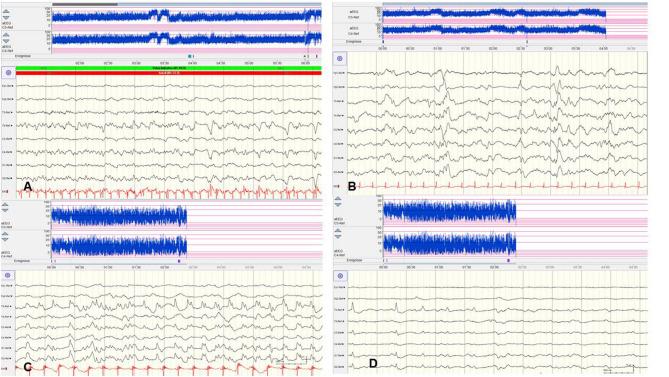

Considering the wide spectrum of etiologies of neonatal-onset epileptic encephalopathies (EE) and their unfavorable consequences for neurodevelopmental prognoses, neuromonitoring at-risk neonates is increasingly important. EEG is highly sensitive for early identification of electrographic seizures and abnormal background activity. Amplitude-integrated EEG (aEEG) is recommended as a useful bedside monitoring method but as a complementary tool because of methodical limitations. It is of special significance in monitoring neonates with acute symptomatic as well as structural, metabolic and genetic neonatal-onset EE, being at high risk of electrographic-only and prolonged seizures. EEG/aEEG monitoring is established as an adjunctive tool to confirm perinatal hypoxic-ischemic encephalopathy (HIE). In neonates with HIE undergoing therapeutic hypothermia, burst suppression pattern is associated with good outcomes in about 40% of the patients. The prognostic specificity of EEG/aEEG is lower compared to cMRI. As infants with HIE may develop seizures after cessation of hypothermia, recording for at least 24 h after the last seizure is recommended. Progress in the identification of genetic etiology of neonatal EE constantly increases. However, presently, no specific EEG changes indicative of a genetic variant have been characterized, except for individual variants associated with typical EEG patterns (e.g., ). Long-term monitoring studies are necessary to define and classify electro-clinical patterns of neonatal-onset EE.

考虑到新生儿期起病的癫痫性脑病(EE)病因广泛,且对神经发育预后有不良影响,对高危新生儿进行神经监测愈发重要。脑电图(EEG)对早期识别脑电图痫性发作及背景活动异常高度敏感。振幅整合脑电图(aEEG)因方法学上的局限性,虽被推荐为一种有用的床旁监测方法,但只是一种辅助工具。它在监测急性症状性以及结构性、代谢性和遗传性新生儿期起病的EE的新生儿时具有特殊意义,这些新生儿存在仅表现为脑电图痫性发作和痫性发作持续时间延长的高风险。EEG/aEEG监测已成为确诊围产期缺氧缺血性脑病(HIE)的辅助工具。在接受治疗性低温治疗的HIE新生儿中,爆发抑制模式在约40%的患者中与良好预后相关。与磁共振成像(cMRI)相比,EEG/aEEG的预后特异性较低。由于HIE婴儿在低温治疗结束后可能发生痫性发作,建议在最后一次发作后至少记录24小时。新生儿EE遗传病因识别方面的进展不断增加。然而,目前除了与典型脑电图模式相关的个别变异外,尚未发现指示基因变异的特定脑电图变化。需要进行长期监测研究来定义和分类新生儿期起病的EE的电临床模式。